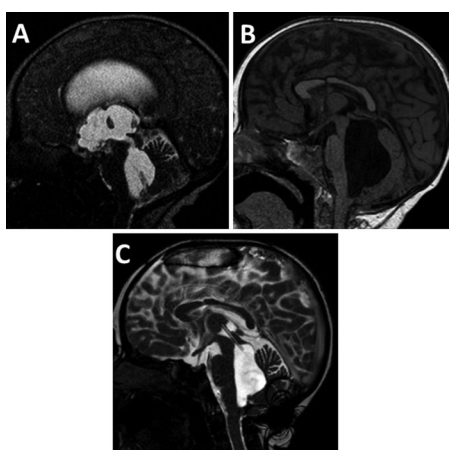

引起AS的外源性病變包括任何占位性病變,如頂蓋板或?qū)?a href='/bingzhong/jiaozhiliu/' target='_blank'>膠質(zhì)瘤、松果體病變和后顱窩腫瘤,以及可能直接壓迫導(dǎo)水管并降低導(dǎo)水管的腦血管畸形(成人很少有Galen靜脈瘤、動(dòng)靜脈畸形、梭形基底動(dòng)脈瘤)流明。此外,不能直接壓迫導(dǎo)水管的占位性病變,如后顱窩腫瘤,可引起經(jīng)小腦幕向上疝及導(dǎo)水管繼發(fā)性變形或壓迫,導(dǎo)致導(dǎo)水管狹窄。有趣的是,當(dāng)壓迫持續(xù)時(shí),由于膠質(zhì)組織和室管膜的二次改變,暫時(shí)性狹窄可能成為長(zhǎng)期性的(Cinalli等人,1999a)(圖2)。

圖2,為繼發(fā)于四邊形蛛網(wǎng)膜囊腫(a)。在ETV后(注意通過(guò)氣孔的流空(b)),導(dǎo)水管的下三分之一處出現(xiàn)狹窄,較終由慢性壓迫引起(c)

功能性AS的治療值得特別注意。由于這種情況是由于幕上和幕下隔室之間的負(fù)壓梯度造成的,隨著導(dǎo)水管的變形/壓縮,提高所容納的腦脊液分流裝置的開啟壓力可以通過(guò)抵消壓力梯度來(lái)重新打開導(dǎo)水管(Raimondi等人,1969年)。另一方面,內(nèi)窺鏡下導(dǎo)水管成形術(shù)可以考慮當(dāng)功能性AS與膠質(zhì)增生相關(guān)時(shí),同時(shí)提高分流的開放壓力(圖3)。

圖3:分流術(shù)治療感染后四室性腦積水;注意矢狀面(a)導(dǎo)水管通暢。功能性AS,四腦室被困(b)。帶支架導(dǎo)水管成形術(shù)治療AS(c)